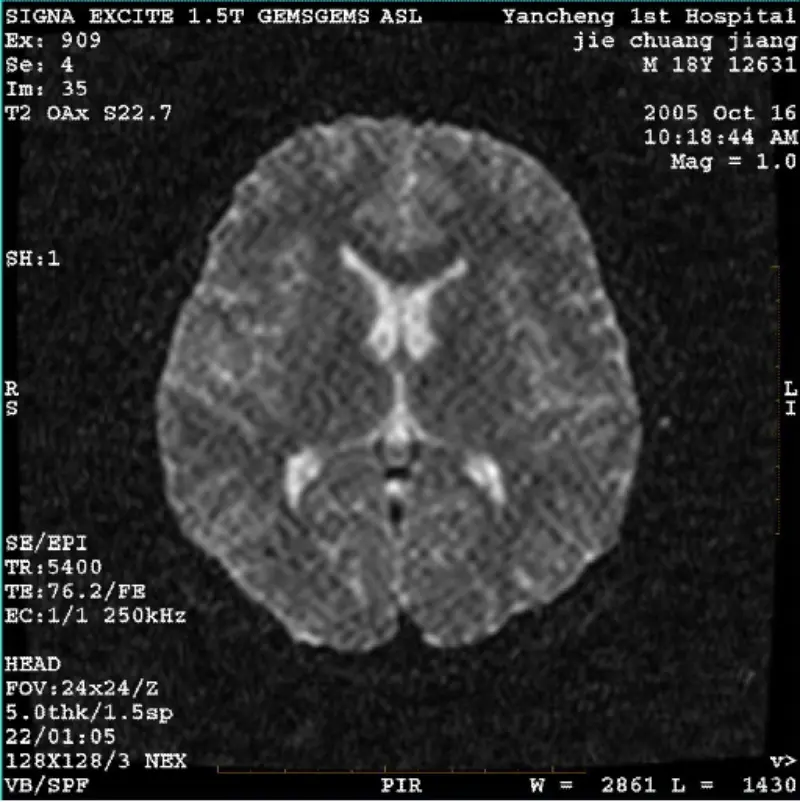

Прочитај повеќеСИСТЕМ: 1.5T Signa Twin Excite II (верзија на софтвер 11.0M4) ПРОБЛЕМ/СИМПТО DWI (режим на зумирање и цел режим) и фиеста (режим на зумирање и целосен режим) слика што има видлив мрежест или сомотски артефакт без разлика кога се користи калем за тело или глава серпентина, друга рутинска слика......